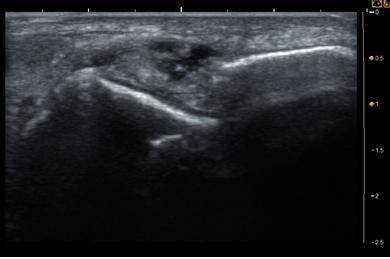

![발목인대손상 초음파소견. [사진 유재욱]](https://img3.daumcdn.net/thumb/R658x0.q70/?fname=https://t1.daumcdn.net/news/201806/21/joongang/20180621172508470niss.jpg)

"발목인대가 다쳐있는데다 쉬어줘야 하는데 계속 무리해서 써서 그래요. 좀 어떻게 변했는지 초음파로 한번 봅시다. 어휴, 이것봐. 발목인대가 파열되고 염증이 생겼잖아. 이러면 발목이 아플 뿐만 아니라, 발목의 안정성이 떨어져서 발목이 흔들리게 되거든. 이렇게 발목 불안정성이 계속되면 나중에는 발목관절까지도 상할 수가 있어요. 발목관절까지 안 좋아지면 수술을 해야 할 정도로 진행할 수도 있으니 지금 정신 차리고 관리를 잘해야 해요."